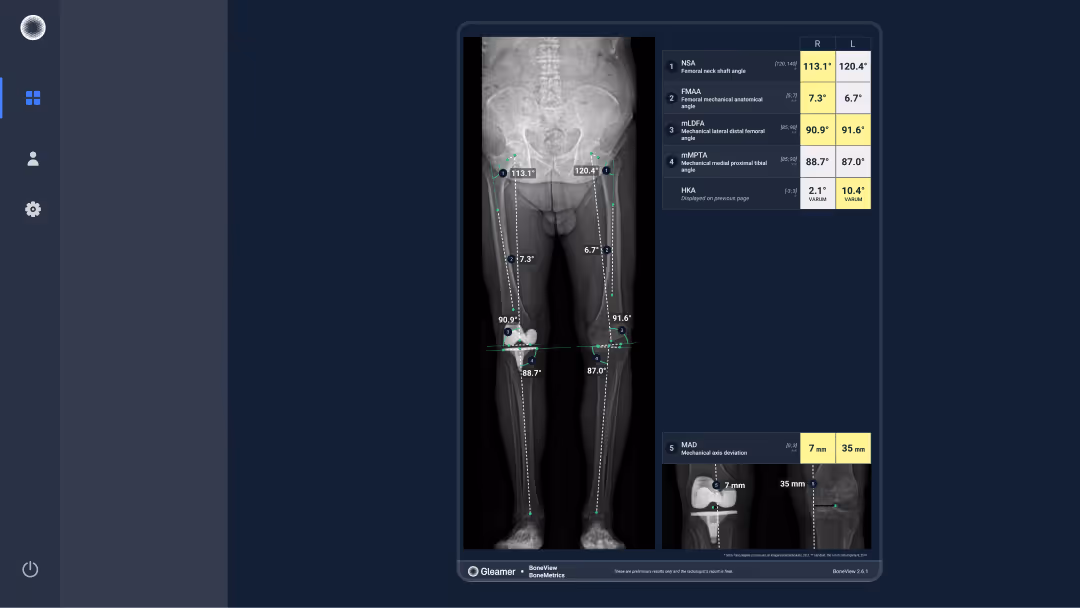

A 78-year-old male presenting with left medial knee pain, undergoing evaluation prior to potential prosthesis placement

Results

BoneMetrics measured a left genu varum deformity, consistent with varus malalignment of the knee.

Hip-knee-ankle angle (HKA)

Femur length (from top and from center)

Tibia length

Leg length (from top and from center)

Pelvic obliquity

Joint Line Obliquity (JLO)

Joint Line Convergence Angle (JLCA)

Mechanical Axis Deviation (MAD)

Femoral Mechanical Anatomical Angle (FMAA)

Mechanical Lateral Distal Tibial Angle (mLDTA)

mechanical Medial Proximal Tibia Angle (mMPTA)

mechanical Lateral Distal Femoral Angle (mLDFA)

mechanical Lateral Proximal Femoral Angle (mLPFA)